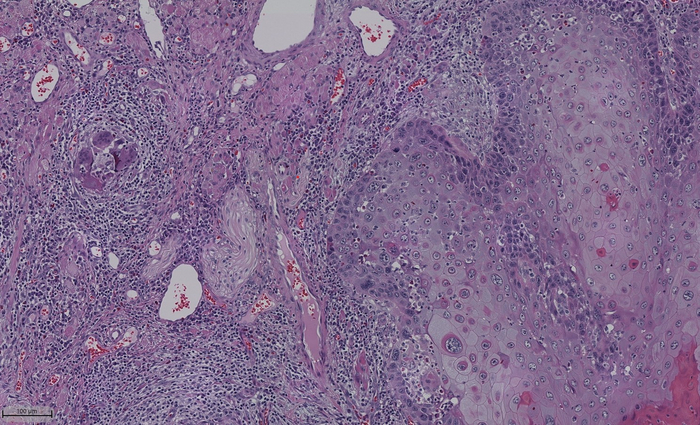

The team created a standardized metric for nerve density to clarify the variation in the distribution of nerves in the oral cavity, called normalized nerve density, and showed its importance in tumor progression. Image Credit: Cindy Perez-Pacheco

To account for this, the team created a standardized metric for nerve density to clarify the variation in the distribution of nerves in the oral cavity, called normalized nerve density and showed its importance in tumor progression. Most of the work was done with human tissue, and the team then validated the findings using a mouse model.

They used adjacent tissue to compare and determine a "normalized" density for different regions in the oral cavity. "We showed that tumors with high normalized nerve density seem to be associated with poor survival for patients with tongue cancer, which is the most common type of oral cancer," D'Silva explained. "We also found that patients with high normalized nerve density and a smaller distance between the nerve and the tumor have poorer outcomes."